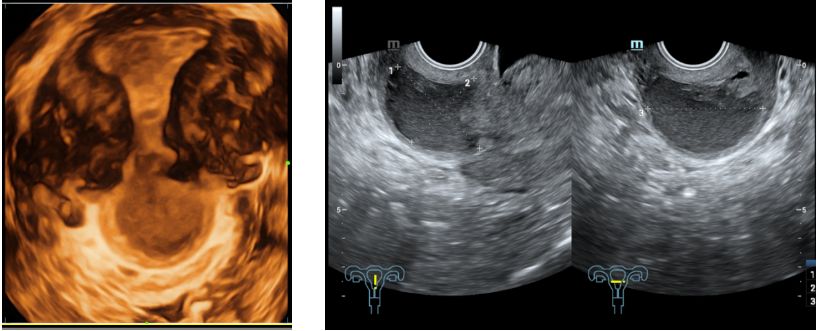

2019-12-30本院经阴道三维子宫附件超声检查示:子宫后位,正常大,内膜厚0.9cm(双层)。前峡部见4.0*3.1cm液性暗区,与宫腔相通,内液稠,宫腔内见多个偏强回声,较大约位于下段1.0*0.9*0.3cm,内见血流。余宫壁回声均匀。双卵巢正常大,回声无殊。右卵巢内见1.8*1.3*2.0cm囊性回声,内液稠。诊断结果:子宫正常大,前峡部暗区(合并内异病灶待排),宫腔多发偏强回声(息肉考虑),右卵巢内囊性块(内异囊肿考虑)。

2020-01-03本院盆腔MRI增强扫描示:子宫峡部-宫颈管见大小约4.2cmx3.6cmx2.9cm囊性肿块,边界清楚,内部可见分隔及分层样改变,增强扫描未见明显强化,局部肌层厚约0.2cm。右侧卵巢内见1.4cmx1.6x1.2cm类似信号影。子宫内膜厚约0.55cm,信号不均,增强扫描未见宫腔内异常强化影。左侧卵巢大小及信号未见明显异常。盆腔淋巴结未见明显肿大。盆腔少量积液。诊断结果:1.子宫峡部-宫颈管内囊性灶,考虑内异囊肿。2.右卵巢内异囊肿。3.子宫内膜信号不均,请结合临床。